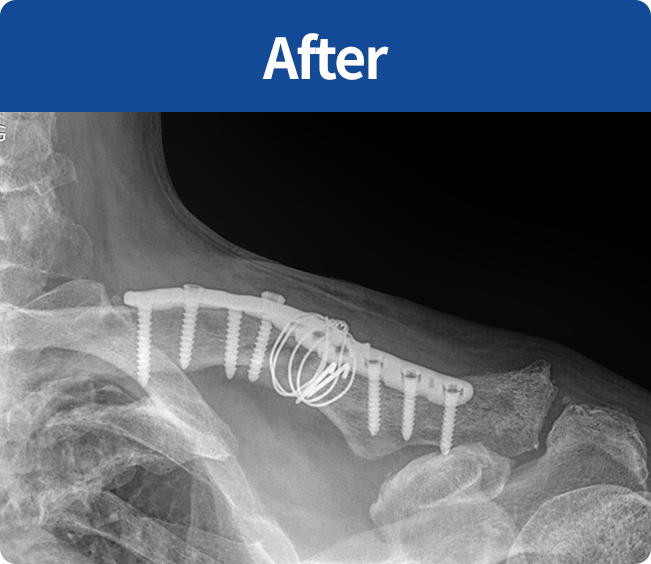

골절 고정술

부러진 뼈를 해부학적 위치로 정확하게 맞춘 뒤,

뼈가 안정적으로 붙을 수 있도록

금속판, 나사, 핀 등을 이용해

고정하는 수술(내고정술, 외고정술)

뼈가 안정적으로 붙을 수 있도록 금속판, 나사, 핀 등을 이용해 고정하는 수술

(내고정술, 외고정술)